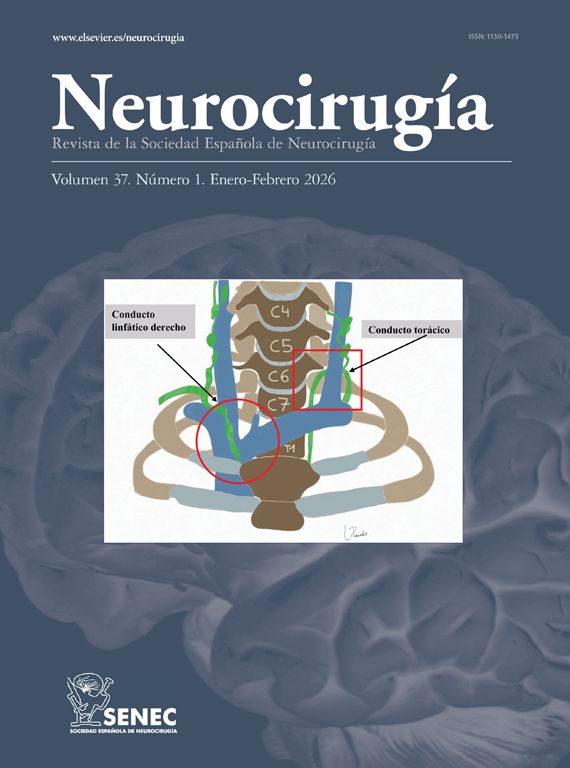

Intracranial hypertension due to central venous stenosis (CVS) is an under-recognized but potentially morbid complication of central venous catheters that can have a benign course if recognized and treated early. Here we report a case of a 23-year-old woman requiring hemodialysis via right subclavian catheter who presented with an intracranial hypertension syndrome and sudden visual loss secondary to right innominate vein thrombosis that improved after angioplasty treatment. This case illustrates how CVS can alter the pressure gradient between the subarachnoid space and the cerebral venous sinuses by increasing venous pressure, affecting cerebrospinal fluid drainage. Since CVS is a common finding in patients receiving hemodialysis, intracranial hypertension due to central venous stenosis is a differential diagnosis to consider in patients of this type who present with intracranial hypertension syndrome.

La hipertensión intracraneal debida a estenosis venosa central (CVS) es una complicación poco reconocida pero potencialmente mórbida de los catéteres venosos centrales que puede tener un curso benigno si se reconoce y trata tempranamente. Presentamos el caso de una mujer de 23 años que requirió hemodiálisis mediante catéter subclavio derecho y que presentó un síndrome de hipertensión intracraneal y pérdida súbita de visión secundaria a trombosis de la vena innominada derecha que mejoró después del tratamiento con angioplastia. Este caso ilustra cómo la CVS puede alterar el gradiente de presión entre el espacio subaracnoideo y los senos venosos cerebrales al aumentar la presión venosa, afectando el drenaje del líquido cefalorraquídeo. Dado que la CVS es un hallazgo común en pacientes que reciben hemodiálisis, la hipertensión intracraneal debida a estenosis venosa central es un diagnóstico diferencial a considerar en pacientes de este tipo que presentan síndrome de hipertensión intracraneal.